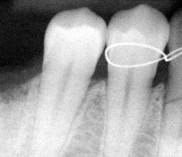

Chirurgia dentystyczna zajmuje się leczeniem operacyjnym jamy ustnej, zębów i tkanek otaczających. Znaczna większość zabiegów z zakresu chirurgii stomatologicznej jest wykonywana w znieczuleniu miejscowym .Dental Park jako jeden z nielicznych oferuje również wykonywanie zabiegów pod narkozą. Najpowszechniejszym zabiegiem z zakresu chirurgii stomatologicznej jest usunięcie zęba czyli ekstrakcja, ale chirurgia stomatologiczna to także zaawansowane zabiegi jak implanty czy wyłuszczanie torbieli kości.

Chirurg stomatolog posiada wieloletnie doświadczenie i w swojej karierze spotkał się z najtrudniejszymi przypadkami. W gabinecie wykonywane jest usuwanie zębów w znieczuleniu miejscowym oraz w narkozie co zapewnia całkowicie bezbolesny zabieg. Pracownia stomatologiczna usuwa zęby mądrości, złamane korzenie. Bardzo często naszymi pacjentami są osoby, które usuwają zęby ze wskazań ortodontycznych. Wykonujemy również zabiegi odbudowy kości jako przygotowanie do leczenia implantologicznego. Nasi pacjenci mogą zawsze liczyć na szybką pomoc w przypadku ropnia, ostrego bólu lub urazu. Chirurg stomatolog zajmuje się wszystkimi nawet najbardziej skomplikowanymi przypadkami.

- resekcje wierzchołka korzenia zęba